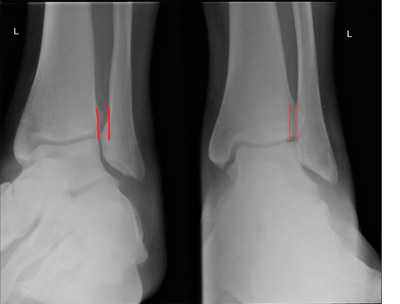

Хирургическую операцию делают при разрыве предней и задней связок межберцового синдесмоза, разрыве связок с расхождением берцовых костей более 2 мм, разрыве связок с нарушением функции голеностопного сустава. При остром повреждении синдесмоза, который дает нестабильность, делают операцию, в ходе которой репонируют малоберцовую кость в вырезку большеберцовой и фиксируют кости винтом. При разрыве синдесмоза в сочетании с переломом берцовых костей и переломо-вывихом голеностопного сустава делают остеосинтез обеих берцовых костей и фиксацию синдесмоза путем стяжки вилки голеностопного сустава. При хронической нестабильности, вызванной разрывом синдесмоза, делают такие операции, как реконструкция передней, задней и межкостной связок синдесмоза, тенодез короткой малоберцовой мышцы, аутопластику трансплантатом из сухожилия длинной малоберцовой мышцы, аллопластику с помощью синтетических связок. После вмешательства накладывают гипсовую иммобилизацию. Для восстановления целостности синдесмоза делают операцию фиксацию межберцового синдесмоза винтами или стягивают берцовые кости с помощью связки. Кости временно свинчивают с помощью компрессионного винта на 6 недель. Нога находится в гипсовой повязке в течение 3 недель. После снятия гипса на ногу надевают ортез или тутор. Тутор ограничивает движения стопы в сагиттальной плоскости и оказывает компрессионное воздействие на лодыжки. Благодаря давлению на берцовые кости с двух сторон поддерживается необходимое расстояние между ними, что способствует срастанию связок синдесмоза.

Рис. 8. Устранение разрыва межберцового синдесмоза после операции фиксации винтами